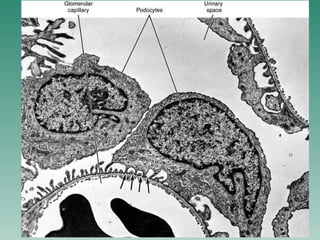

The document discusses the microscopic structure of the urinary system, including the nephron, renal parenchyma, components of the renal parenchyma, histotopography of the nephron, renal corpuscle, podocytes, filtration membrane, uriniferous tubule, loop of Henle, collecting tubules, medulla renis, juxtaglomerular apparatus, macula densa, juxtaglomerular cells, and blood circulation of the kidney. It also briefly mentions the stages in development of the kidneys, including the pronephros, mesonephros, and metanephros.